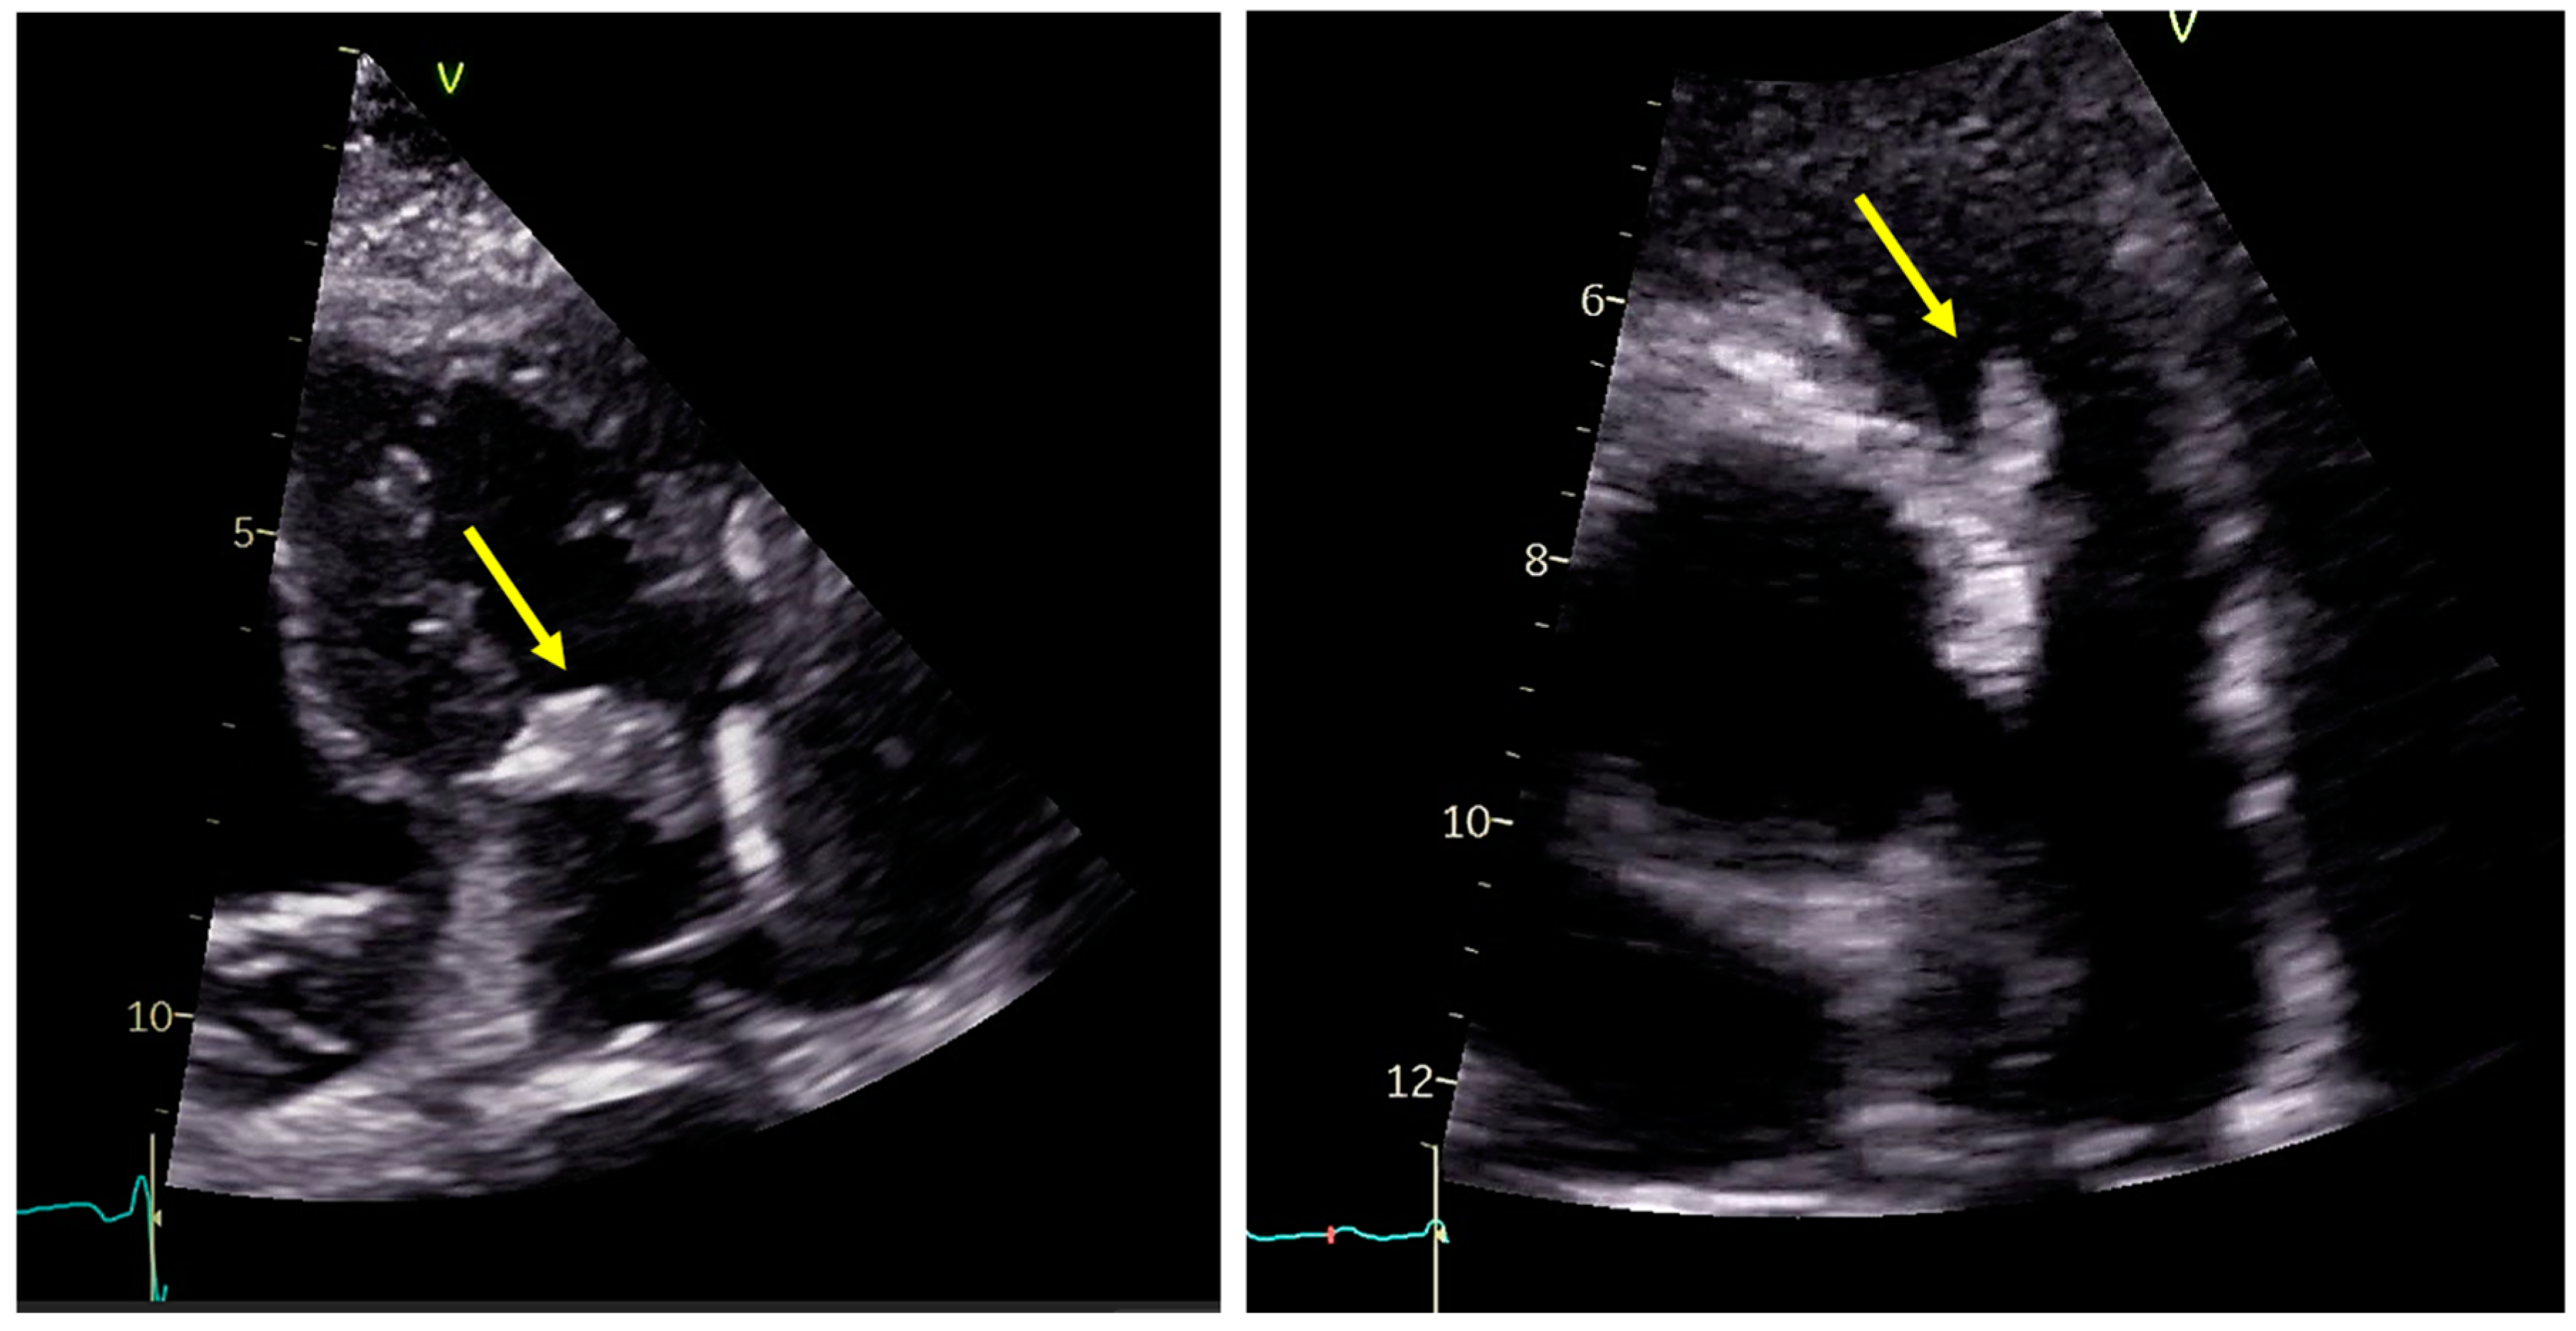

3.2. Role of Echocardiography

- Fusco, F.; Scognamiglio, G.; Correra, A.; Merola, A.; Colonna, D.; Palma, M.; Romeo, E.; Sarubbi, B. Pulmonary valve endocarditis in adults with congenital heart disease: The role of echocardiography in a case series. Eur. Heart J. Case Rep. 2020, 4, 1–7. [Google Scholar] [CrossRef]